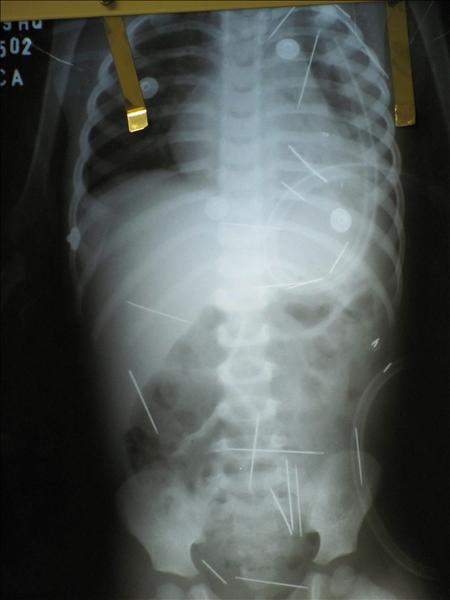

El domingo, el pequeño fue sometido a exámenes más detallados en otro hospital de la ciudad de Barreirinhas, donde las radiografías revelaron que tiene en total 50 objetos metálicos esparcidos por todo el cuerpo entre el abdomen, el cuello, el tórax y hasta las piernas.

Un último informe médico reveló, además, que una de las agujas le perforó un pulmón al menor, que continúa ingresado en estado grave.